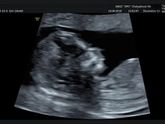

Всем привет! Знаю есть такая примета беременным ни шить, ни вязать нельзя. Я не верила и в первую беременность немного вязала, ребёнок обвился пуповиной, не много но все же. Во вторую пелёнок решила нашить, в итоге органы были готовы к родам, а процесс … Читать далее